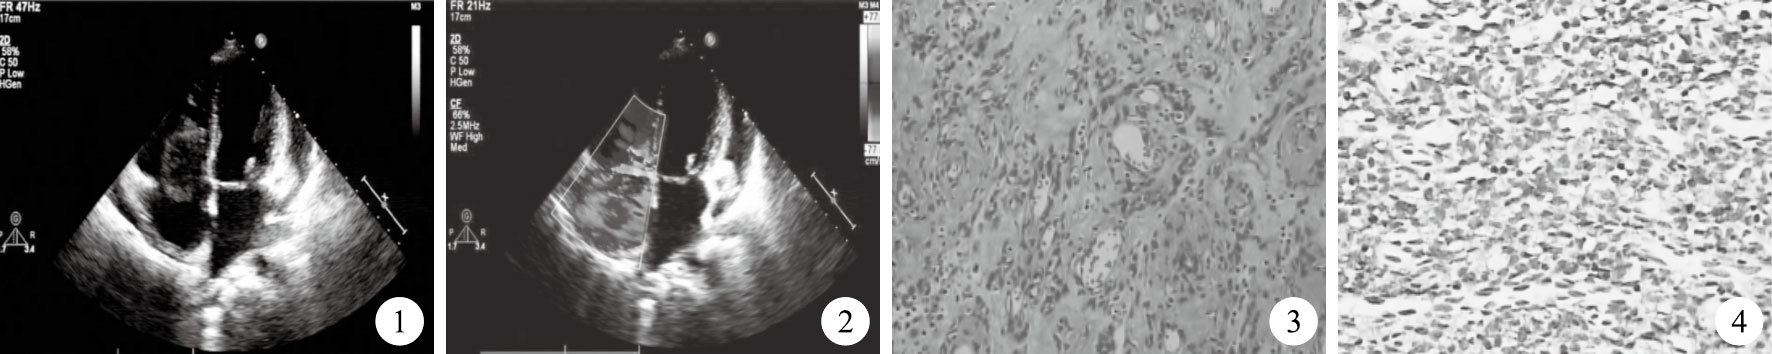

患者6年后起再次出現活動后頭暈、胸悶,到我院就診,心臟聽診胸骨左緣第4肋間可聞及3/6級收縮期雜音,心臟彩色超聲心動圖提示:左心房、右心房擴大,右心房內見一實質性等回聲光團,大小約4.4 cm×2.7 cm,邊界清,內部回聲尚均勻,可見由蒂連接于房間隔,隨心動周期于右心房、右心室內擺動(圖 1)。心包腔中量積液。彩色多普勒檢查探及三尖瓣大量反流,反流束充滿整個右心房(圖 2)。患者血常規、腫瘤指標等化驗結果未見異常;排除手術禁忌證后在氣管內插管吸入+靜脈全身麻醉、體外循環下行右心房腫瘤切除術,術中心內結構探查見右心房內可見不規則分葉狀腫瘤,大小約4 cm×3 cm×1.5 cm,瘤體包膜完整,質軟,表面光滑,部分淤血,腫瘤蒂位于心包補片毗鄰冠狀靜脈竇處,蒂直徑約0.5 cm,心臟收縮期通過三尖瓣口落入右心室導致三尖瓣關閉不全、大量反流。完整切除右心房腫瘤,將瘤蒂周圍的內膜擴大切除至直徑約1 cm,再以4-0 Prolene線縫合加固。術后患者心臟自動復跳。手術過程順利。術后病理學檢查及免疫組織化學染色結果示瘤組織由增生的毛細血管和梭形細胞組成,梭形細胞圍繞毛細血管分布,大部分細胞規整,局部細胞核輕度異型性,未見明確核分裂像,間質玻璃樣變性,局部出血、血腫形成(圖 3);免疫組織化學染色(圖 4):MC (+),K灶性 (+),IM (+),A (-),D31 (+),Myogenin (-),D2-40 (-),HHF-35 (-),Ki-67約3% (+),AB/PAS黏液 (-);考慮為右心房間皮瘤,局部細胞生長活躍,伴局部細胞生長活躍和血腫形成。術后予以重癥監護、強心、利尿等治療,患者恢復情況良好,復查心臟彩色超聲心動圖提示右心房未見腫物,房室腔大小正常,心內結構及運動未見異常,術后10 d患者康復出院。